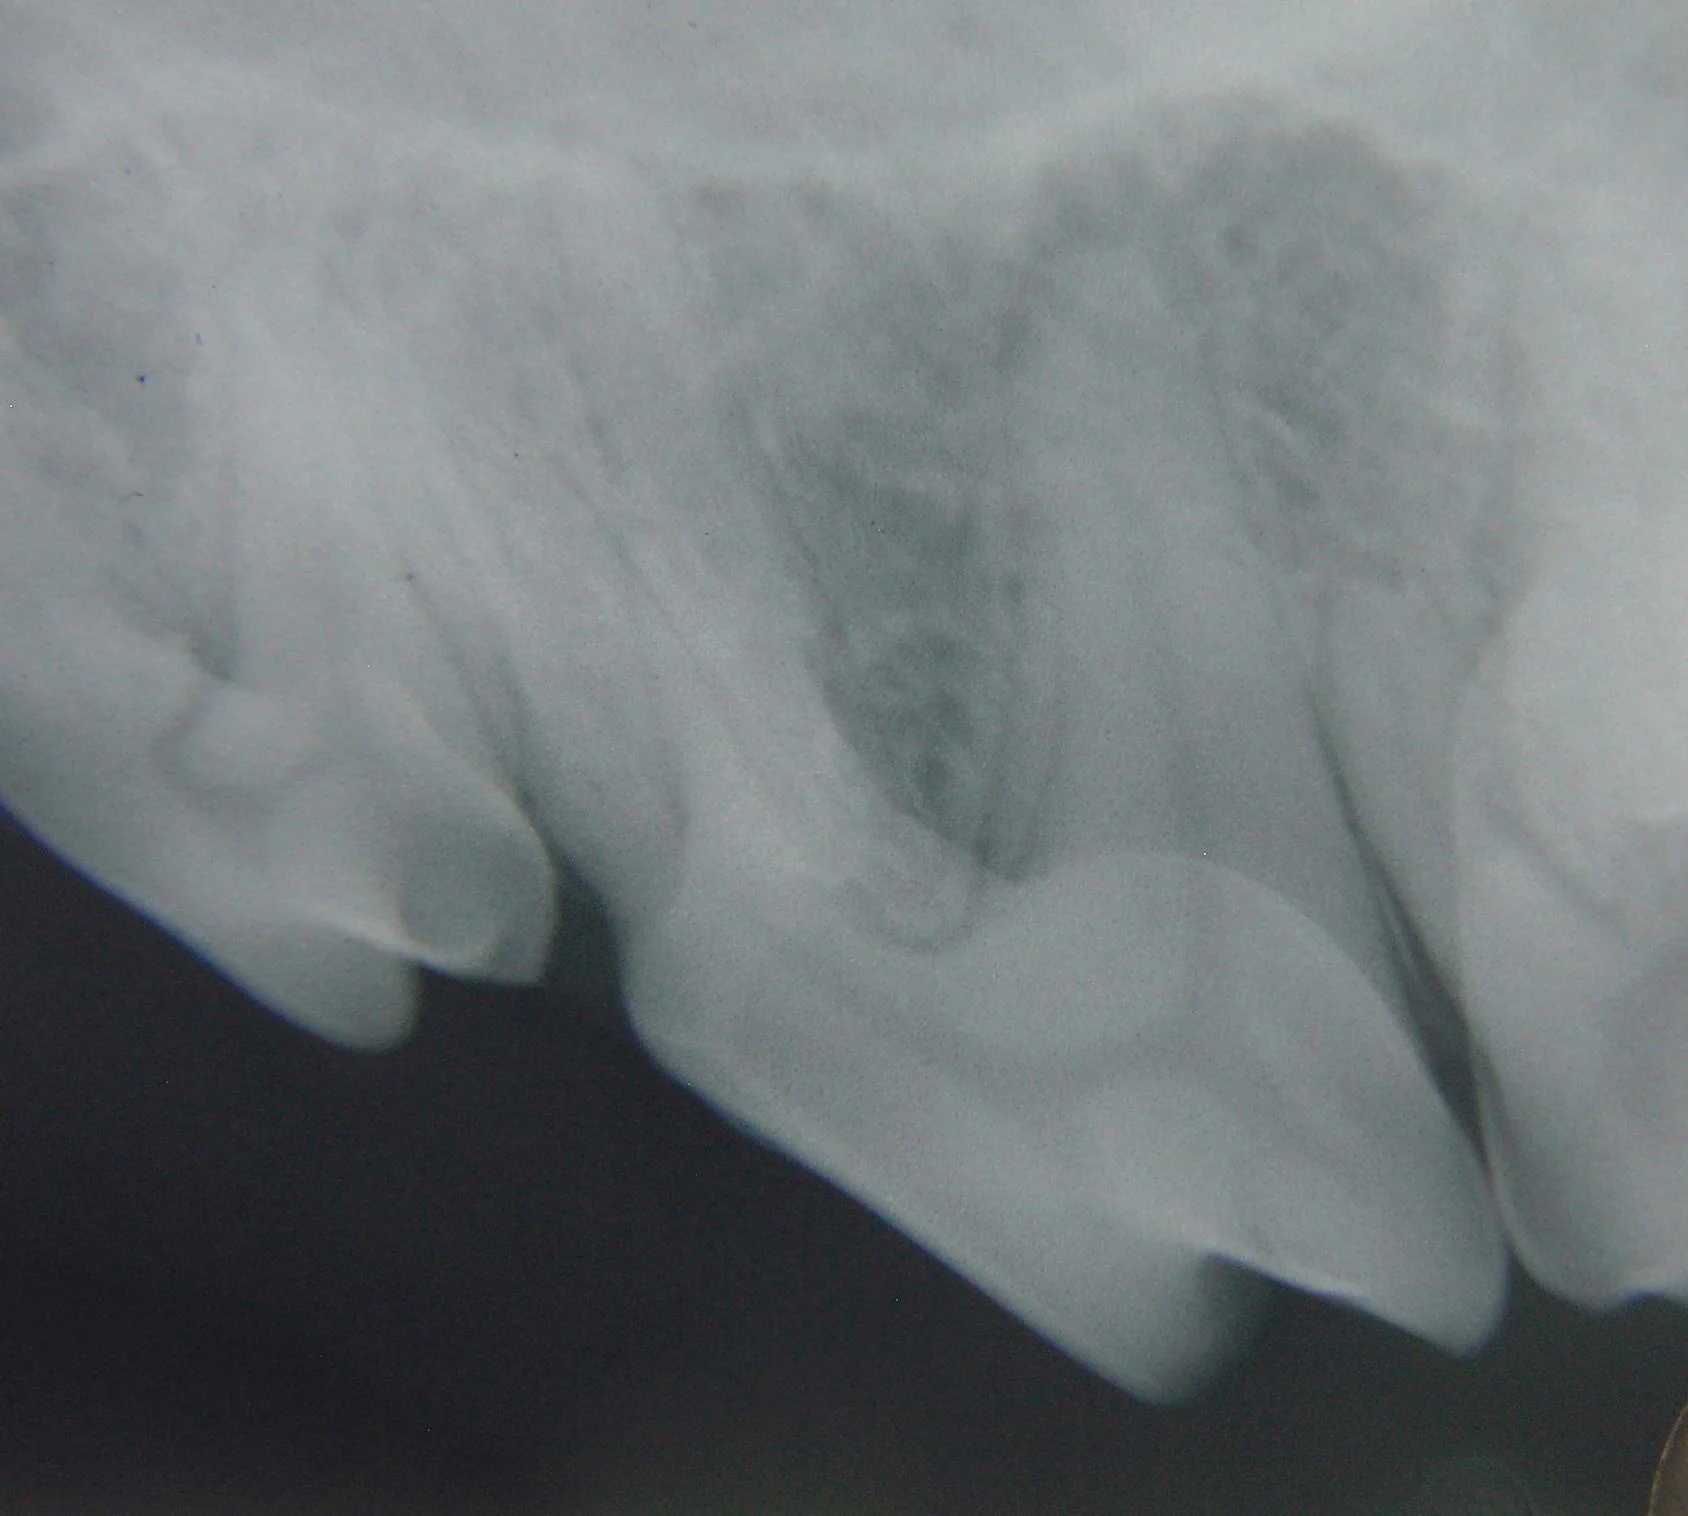

Step 3

Positioning of the x-ray machine tubehead perpendicular to the plane of the dental x-ray film (A, B) would create a foreshortened image of the tooth or roots (B). This image would probably not be diagnostic, but the apex of the palatal root can be seen.